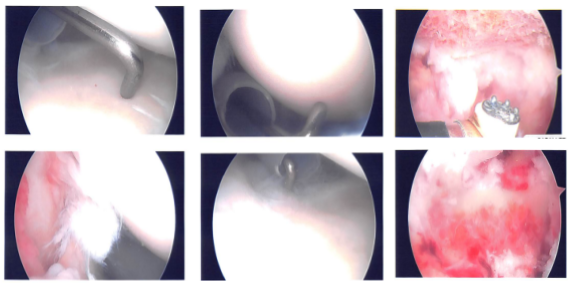

The posterior entry portal was made, which was a soft spot. Arthroscope was entered into the glenohumeral ligament. Anterosuperior portal was also made with the use of Shaver and was introduced from the anterosuperior portal.

There was fraying of the glenoid labrum as well as articular site of the rotator cuff, which were debrided with the use of shaver. There was also partial tearing and fraying of the subscapularis tendon, which was also cleaned with the shaver.

There was no damage. Pictures were taken and saved. The arthroscope was entered into subacromial space. There was subacromial bursitis, which was debrided. There was bleeding and difficulty due to the patient’s weight and size.

Coblation wand was used followed by burr to perform acromioplasty of the right shoulder. Distal clavicle excision was also done with the use of Coblation wand and #6-0 burr. Rotator cuff was not done on the bursal site; so, a decision was made to open the rotator cuff with the use of a Regeneten implant.

Large Regeneten implant was introduced through the lateral portal and was put in place with the use of PLA tacks x8. Final pictures were taken and saved. The shoulder was thoroughly irrigated and drained.

Intraoperative photo